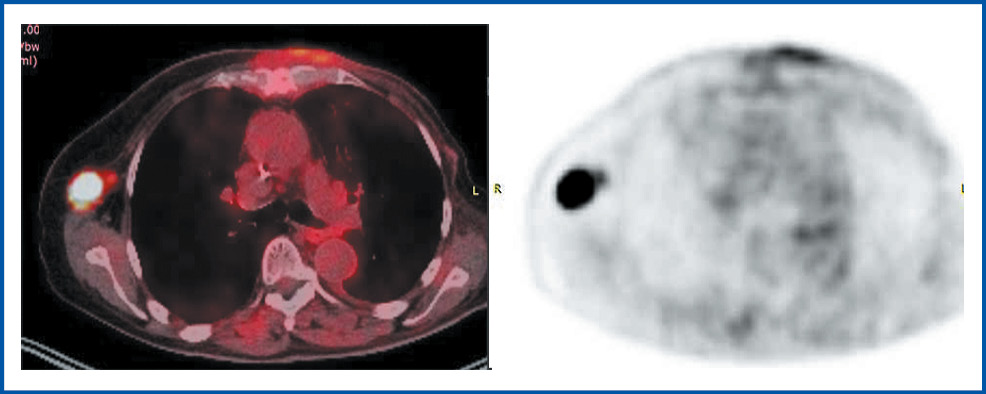

После четырех курсов монохимиотерапии капецитабином при ПЭТ-КТ от мая 2022 г. диагностирована отрицательная динамика в виде роста опухолевых очагов: распадающийся конгломерат на передней грудной стенке до 130×90×120 мм, 18F-фтордезоксиглюкоза (18F-ФДГ) SUVmax 55,07. Отмечено распространение опухоли на рукоятку и тело грудины, с деструкцией костной структуры, инвазией в клетчатку переднего средостения до уровня яремной вырезки. Определяется опухолевое поражение паратрахеального лимфатического узла справа 19×19 мм с накоплением 18F-ФДГ SUVmax 41,68; визуализируется конгломерат парааортальных лимфатических узлов на уровне дуги аорты до 31×33 мм, с накоплением 18F-ФДГ SUVmax 43,44; лимфатические узлы на уровне плечеголовных сосудов до 8 мм с накоплением 18F-ФДГ SUVmax 20,11; единичный парастернальный левый нижний лимфатический узел до 4 мм с накоплением 18F-ФДГ SUVmax 6,97; подключичные, надключичные лимфатические узлы до 12–24 мм с накоплением 18F-ФДГ SUVmax 46,36; нижние яремные лимфатические узлы слева до 13 мм с накоплением 18F-ФДГ SUVmax 47,13 (рис. 1).

Рис. 1. ПЭТ-КТ горизонтальная проекция от мая 2022 г. до начала лечения. Вид грудной стенки на уровне ThIV позвонка.

Fig. 1. PET-CT, horizontal view dated May 2022 before the beginning of treatment. View of the chest wall at the level of the ThIV vertebra.